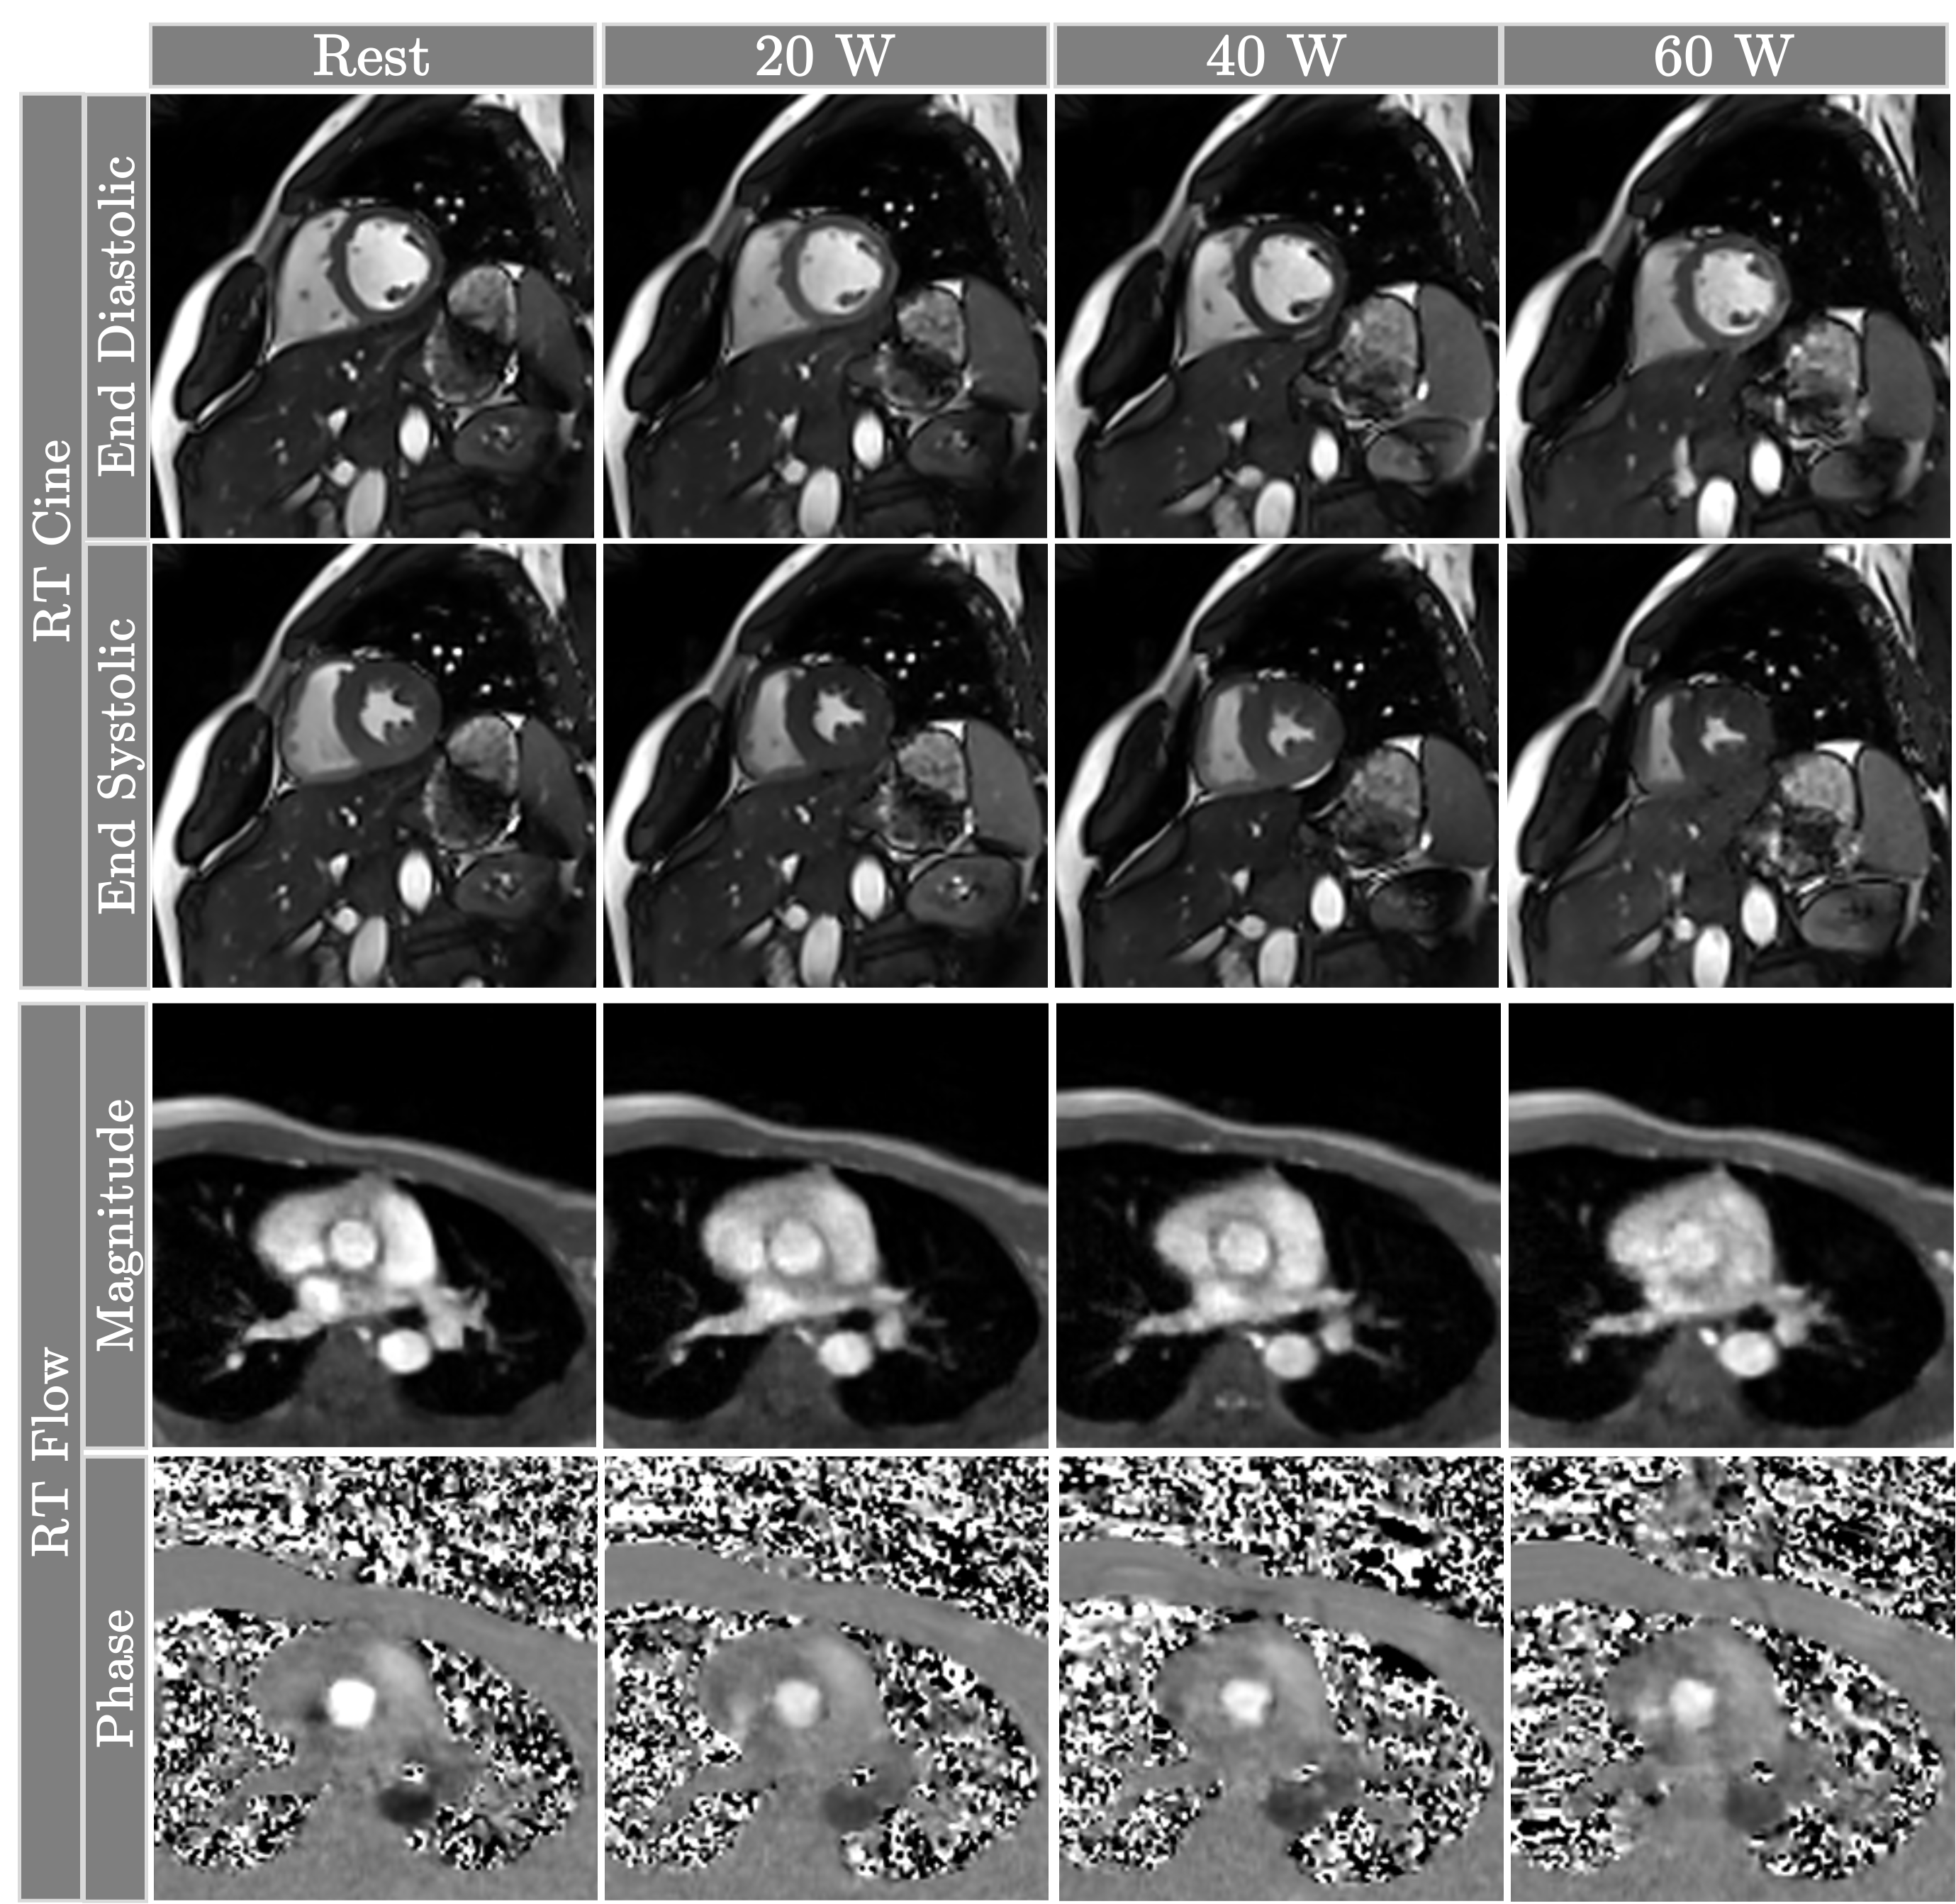

Refer to caption

Figure 3: Representative cine and flow frames from a healthy volunteer at rest and across three stages of exercise. Stronger contractility under exercise stress is observed from end-systolic frames (second row). The brighter phase (bottom row) in the resting image is due to the lower value of VENC.

Figure 2 summarizes the changes in cardiac function and hemodynamic parameters from rest through various stages of exercise. The values of ESV, both for LV and RV, consistently decrease due to more vigorous contractions under stress. The values of EDV remain relatively stable across different exercise intensities. As a result, both SV and EF gradually increase with exercise. Compared to SV, the increase in CO is more pronounced due to the increased HR. This biventricular increase is observed in both cine and flow images. Figure 3 shows an example of RT cine and flow images from a healthy subject. The cine images show a clear delineation of the blood-myocardium boundary, with some marginal blurring at 60 W. The end-systolic frames exhibit stronger contractility, especially at 60 W. The flow images are mostly free of motion artifacts, with the 60 W magnitude images showing marginal blurring.